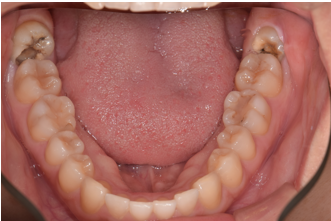

主訴:親知らずが気になる

Before

通院時の年齢 | 44歳 |

---|---|

性別 | 女性 |

通院回数 | 20回程度 8ヶ月 |

通院目的 | 自分の歯を残したい |

処置内容 | アップライト矯正治療 |

費用 | 10万(歯周病治療は保険治療・被せ物は自費診療で今回の費用には含まない) |

デメリット・注意点 | 歯周病にかかっている患者さんは矯正治療を受けられない可能性があります 歯周病にかかっている歯は歯周病の治療が完了してから矯正の可否を判断します うまく矯正治療で動かない場合があります |

備考 | 抜歯になると入れ歯かインプラントを選択しなくてはならず費用は3倍近くかかります 保険の入れ歯は咬むことを阻害してしまうので身体への害はもちろんのことせっかく治療した歯の歯茎がすぐに下がって再度虫歯になってしまう可能性や引っかけの歯に負担が大きくなり抜歯になることがあります |